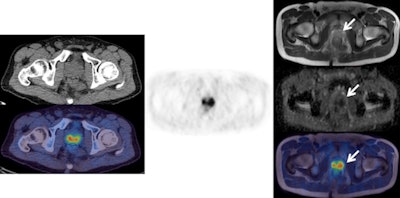

![Left: F-18 choline PET/CT (CT top and fused PET/CT bottom). Center: F-18 choline PET. Right: MRI (from top to bottom: T1, b900 diffusion-weighted image [DWI], apparent diffusion coefficient [ADC] map, fused PET/T1 MRI). These images show an enlarged choline-avid left pelvic lymph node in a man with high-risk Gleason 4+5 prostate cancer. This is clearly seen (arrow) on the PET/CT images, as well as on all the MRI sequences (high signal on b900 and restricted diffusion on ADC map). There is a small equivocal focus of uptake on the PET scan in the right side of the pelvis (arrow head), but it is difficult to confirm this is a lymph node on the CT and fused PET/CT images. The MRI sequences confirm a small lymph node with high signal on b900 DWI and restricted diffusion on ADC map (arrowhead). This case shows how the superior tissue contrast and anatomical resolution of MRI sequences allow a better definition of the cause of the right-sided pelvic PET activity and a much more confident diagnosis of right as well as left lymph node involvement. All images courtesy of Dr. Gary Cook.](https://img.auntminnieeurope.com/files/base/smg/all/image/2016/03/ame.2016_03_04_16_05_50_348_2016_03_05_ECR_Today_PET-MRI1.png?auto=format%2Ccompress&fit=max&q=70&w=400)